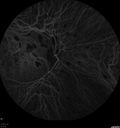

INDOCYANINE GREEN ANGIOGRAPHY: An indocyanine green angiogram was obtained in the both eyes, because of the multifocal chorioditis. The indocyanine green does show hypofluorescence centrally where the neovascular complex is and in the later frames there is a small hypofluorescence lesion. The right eye shows multifocal hypofluorescence spots corresponding to the macular scar.

Punctate Inner Choroidopathy - Recurrent CNVM 4 years after initial treatment Left Eye - Indocyanine Green Angiogram602 viewsJune 7, 2012. This pleasant 35-year-old woman noticed decreasing vision in the left eye recently. She returns now noticing the vision in the left eye is declining. OD 20/50, OS 20/80. OS: Vertical C/D ratio is 0.3. There is a scar just inferonasal to the fovea, which has grown some towards the fovea with a little blood just under the fovea.

(0 votes)